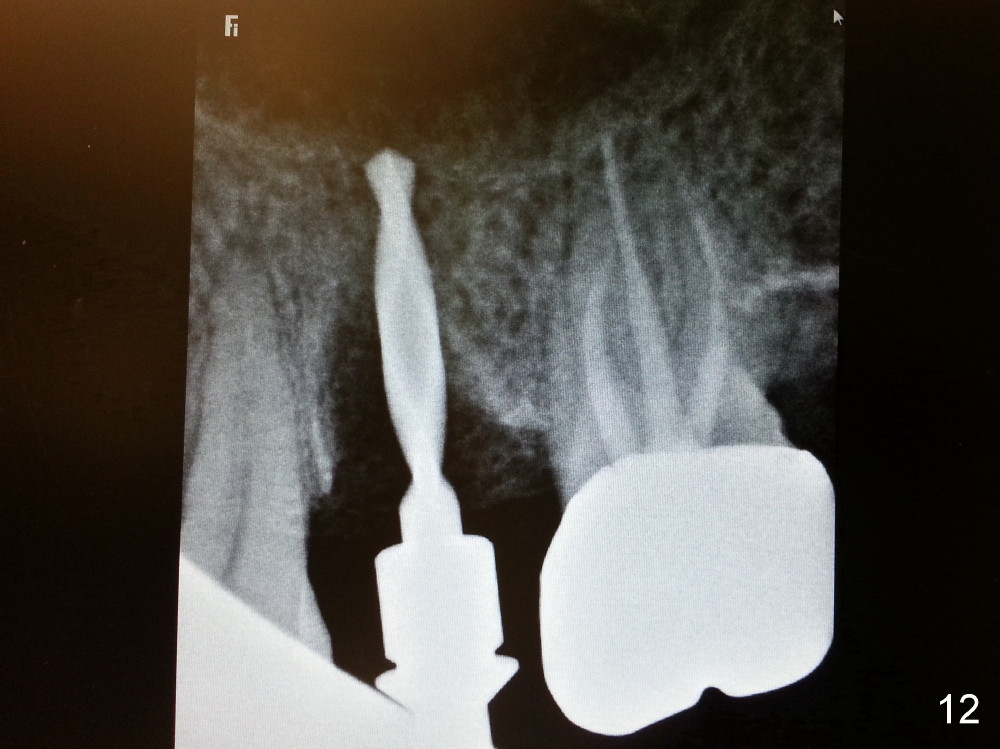

The tooth #13 appears to be affected by periodontits and occlusal trauma (Fig.1*). After using a periotome (Fig.2), the tooth is extracted (Fig.3). The buccal flap is raised (Fig.4). Gingival graft is to be harvested from the site of #15 (Fig.5). The tissue is elevated buccally (Fig.6) and separated (Fig.7). The donor site is covered by a collagen membrane (Fig.8*). A diamond bur is used to induce bleeding from the socket (Fig.9*). Osteotomy is initiated (Fig.10) and enlarged (Fig.11,12). A tapered implant is being placed (Fig.13-15) following internal sinus lift (Fig.16,17). The implant is placed subcrestally, followed by bone graft (Fig.18), soft tissue graft (Fig.19), and suturing (Fig.20 <, Fig.21).